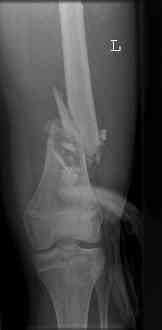

16 yr old boy, high energy motorcycle trauma trauma in July 2005 with:

- hip dislocation + acetabular fracture L

- distal femoral fracture L

- tibial shaft fracture L

- metatarsal fractures L

july 05: LISS femur, LCP plate tibia, double recon. plate post. acetabulum

oct 05: cancellous bone graft femur

aug 06: blade plate + bone graft

nov 06: revision blade plate

feb 07: retrograde nail + bone graft + BMP

may 07: dynamisation nail

sept 07: locking screw removal (max. dynamisation reached)

nov 07: persistant non-union distal femur; other fractures healed uneventfully.

All with gradual/partial weightbearing etc. Currently 50-100% weight bearing, no pain.

Soft tissues are intact. No smoking or diabetes.CRP <2

What would you do?